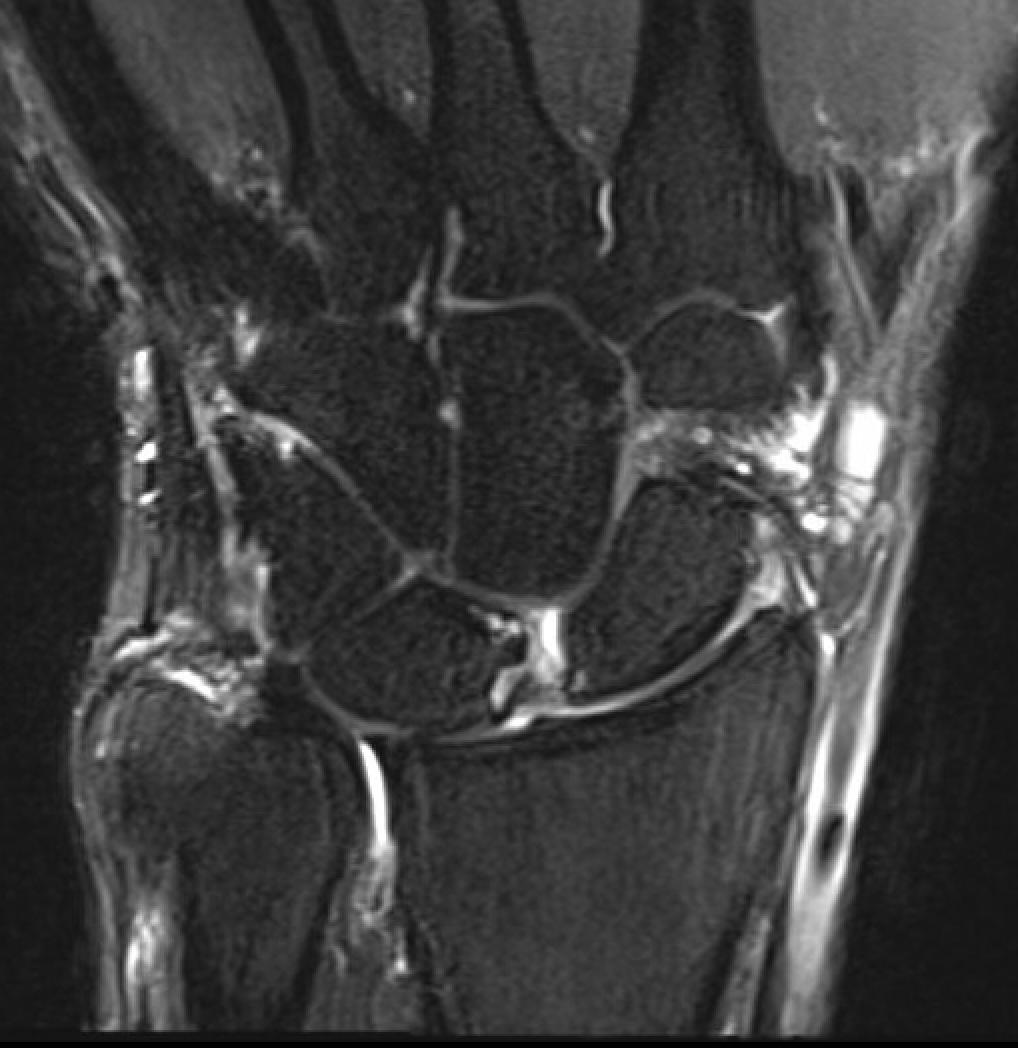

MRI

SL ligament injury with minimal disassociation / SL separation / dynamic instability

SL ligament injury with SL separation and static instability

Increased scapholunate angle